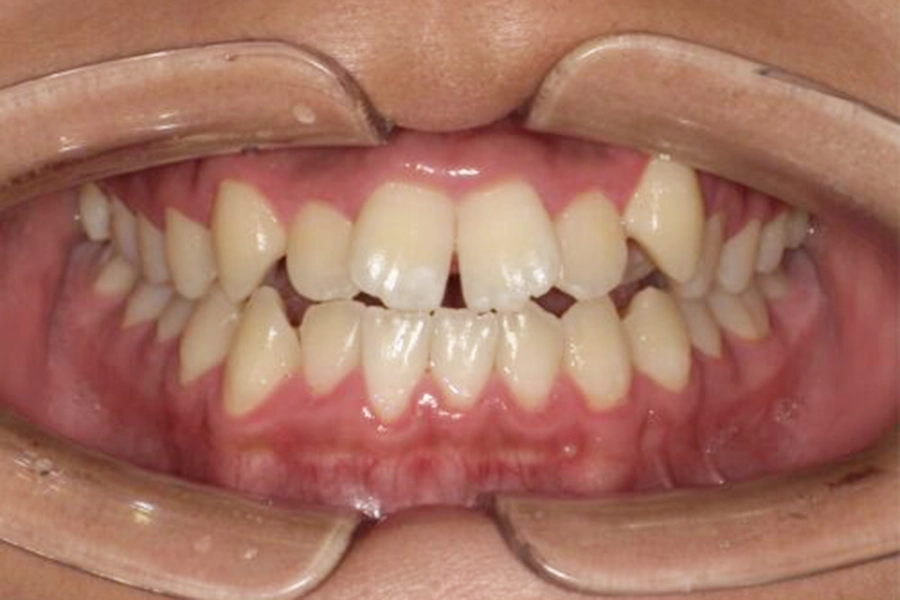

初診時の写真です。

歯茎が上がり、根の部分が露出しているため色が濃く見えます。

また、被せ物と歯との間に段差があるため、着色や汚れが入り込んでいます。